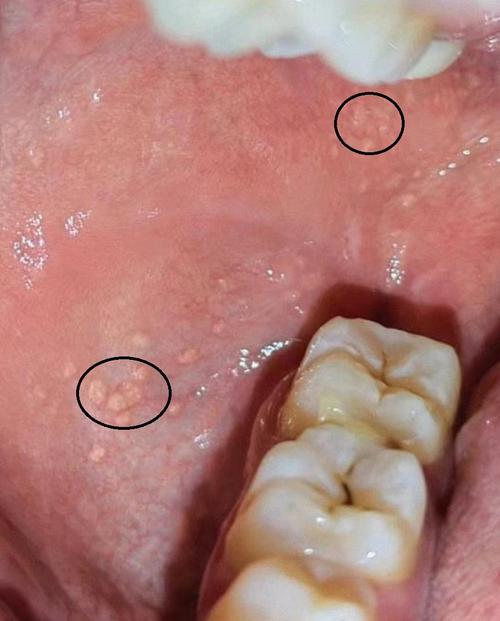

口腔内白色粘膜是何原因?

仅供参考,不能替代专业医疗诊断,如果您发现口腔内有白色粘膜,请务必咨询牙医或口腔科医生,以获得准确诊断和适当治疗。(图片来源网络,侵删) 口腔内白色粘膜的常见类型及图片描述 口腔内的白色粘膜可能由多种原因引起,从无害的生理现象到需要治疗的疾病都有可能,以下是几种主要类型: 生理性/正常现象 a. 角...